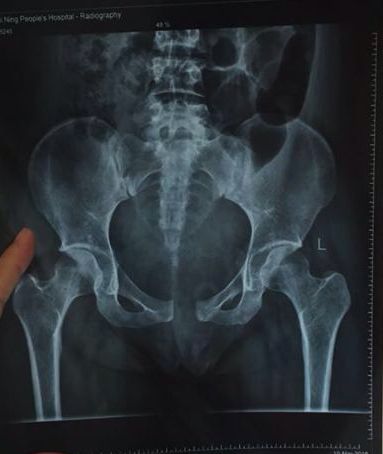

对耻骨联合分离症的认识和一些基本对策

什么是耻骨分离